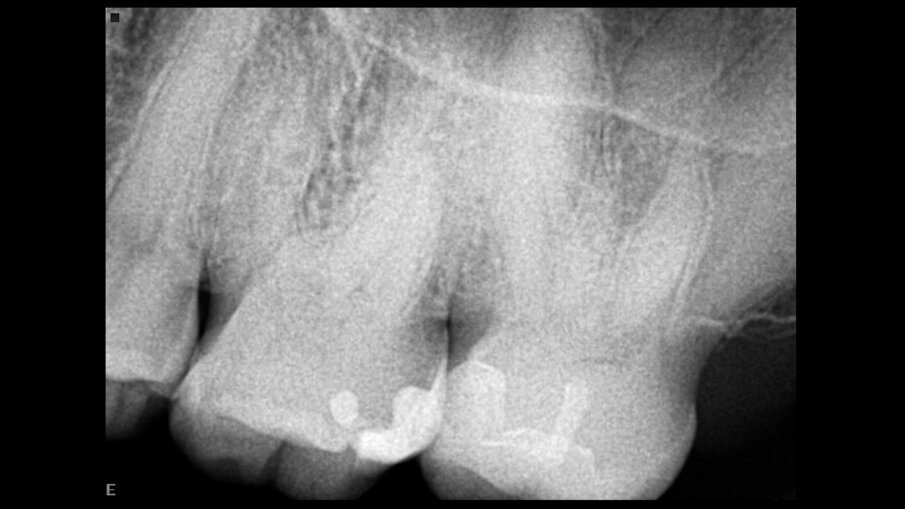

Същият пациент имаше фистула в букалната област на нивото на фуркацията на долен молар в резултат на твърде високите оклузални контакти, които не са били коригирани след поставянето на инлея на горния молар (фиг. 8). Това е довело до активиране на субстанция Р, която впоследствие е създала калцификацията в горния молар и необратимото възпаление на долния молар – ефект на микротравмата.

Фиг. 8а Предоперативна рентгенография, показваща калцирана пулпна камера и нерентгеноконтрастна лезия в областта на фуркацията (а). Фистула, насочена към коронарната част на кореновия канал (б).